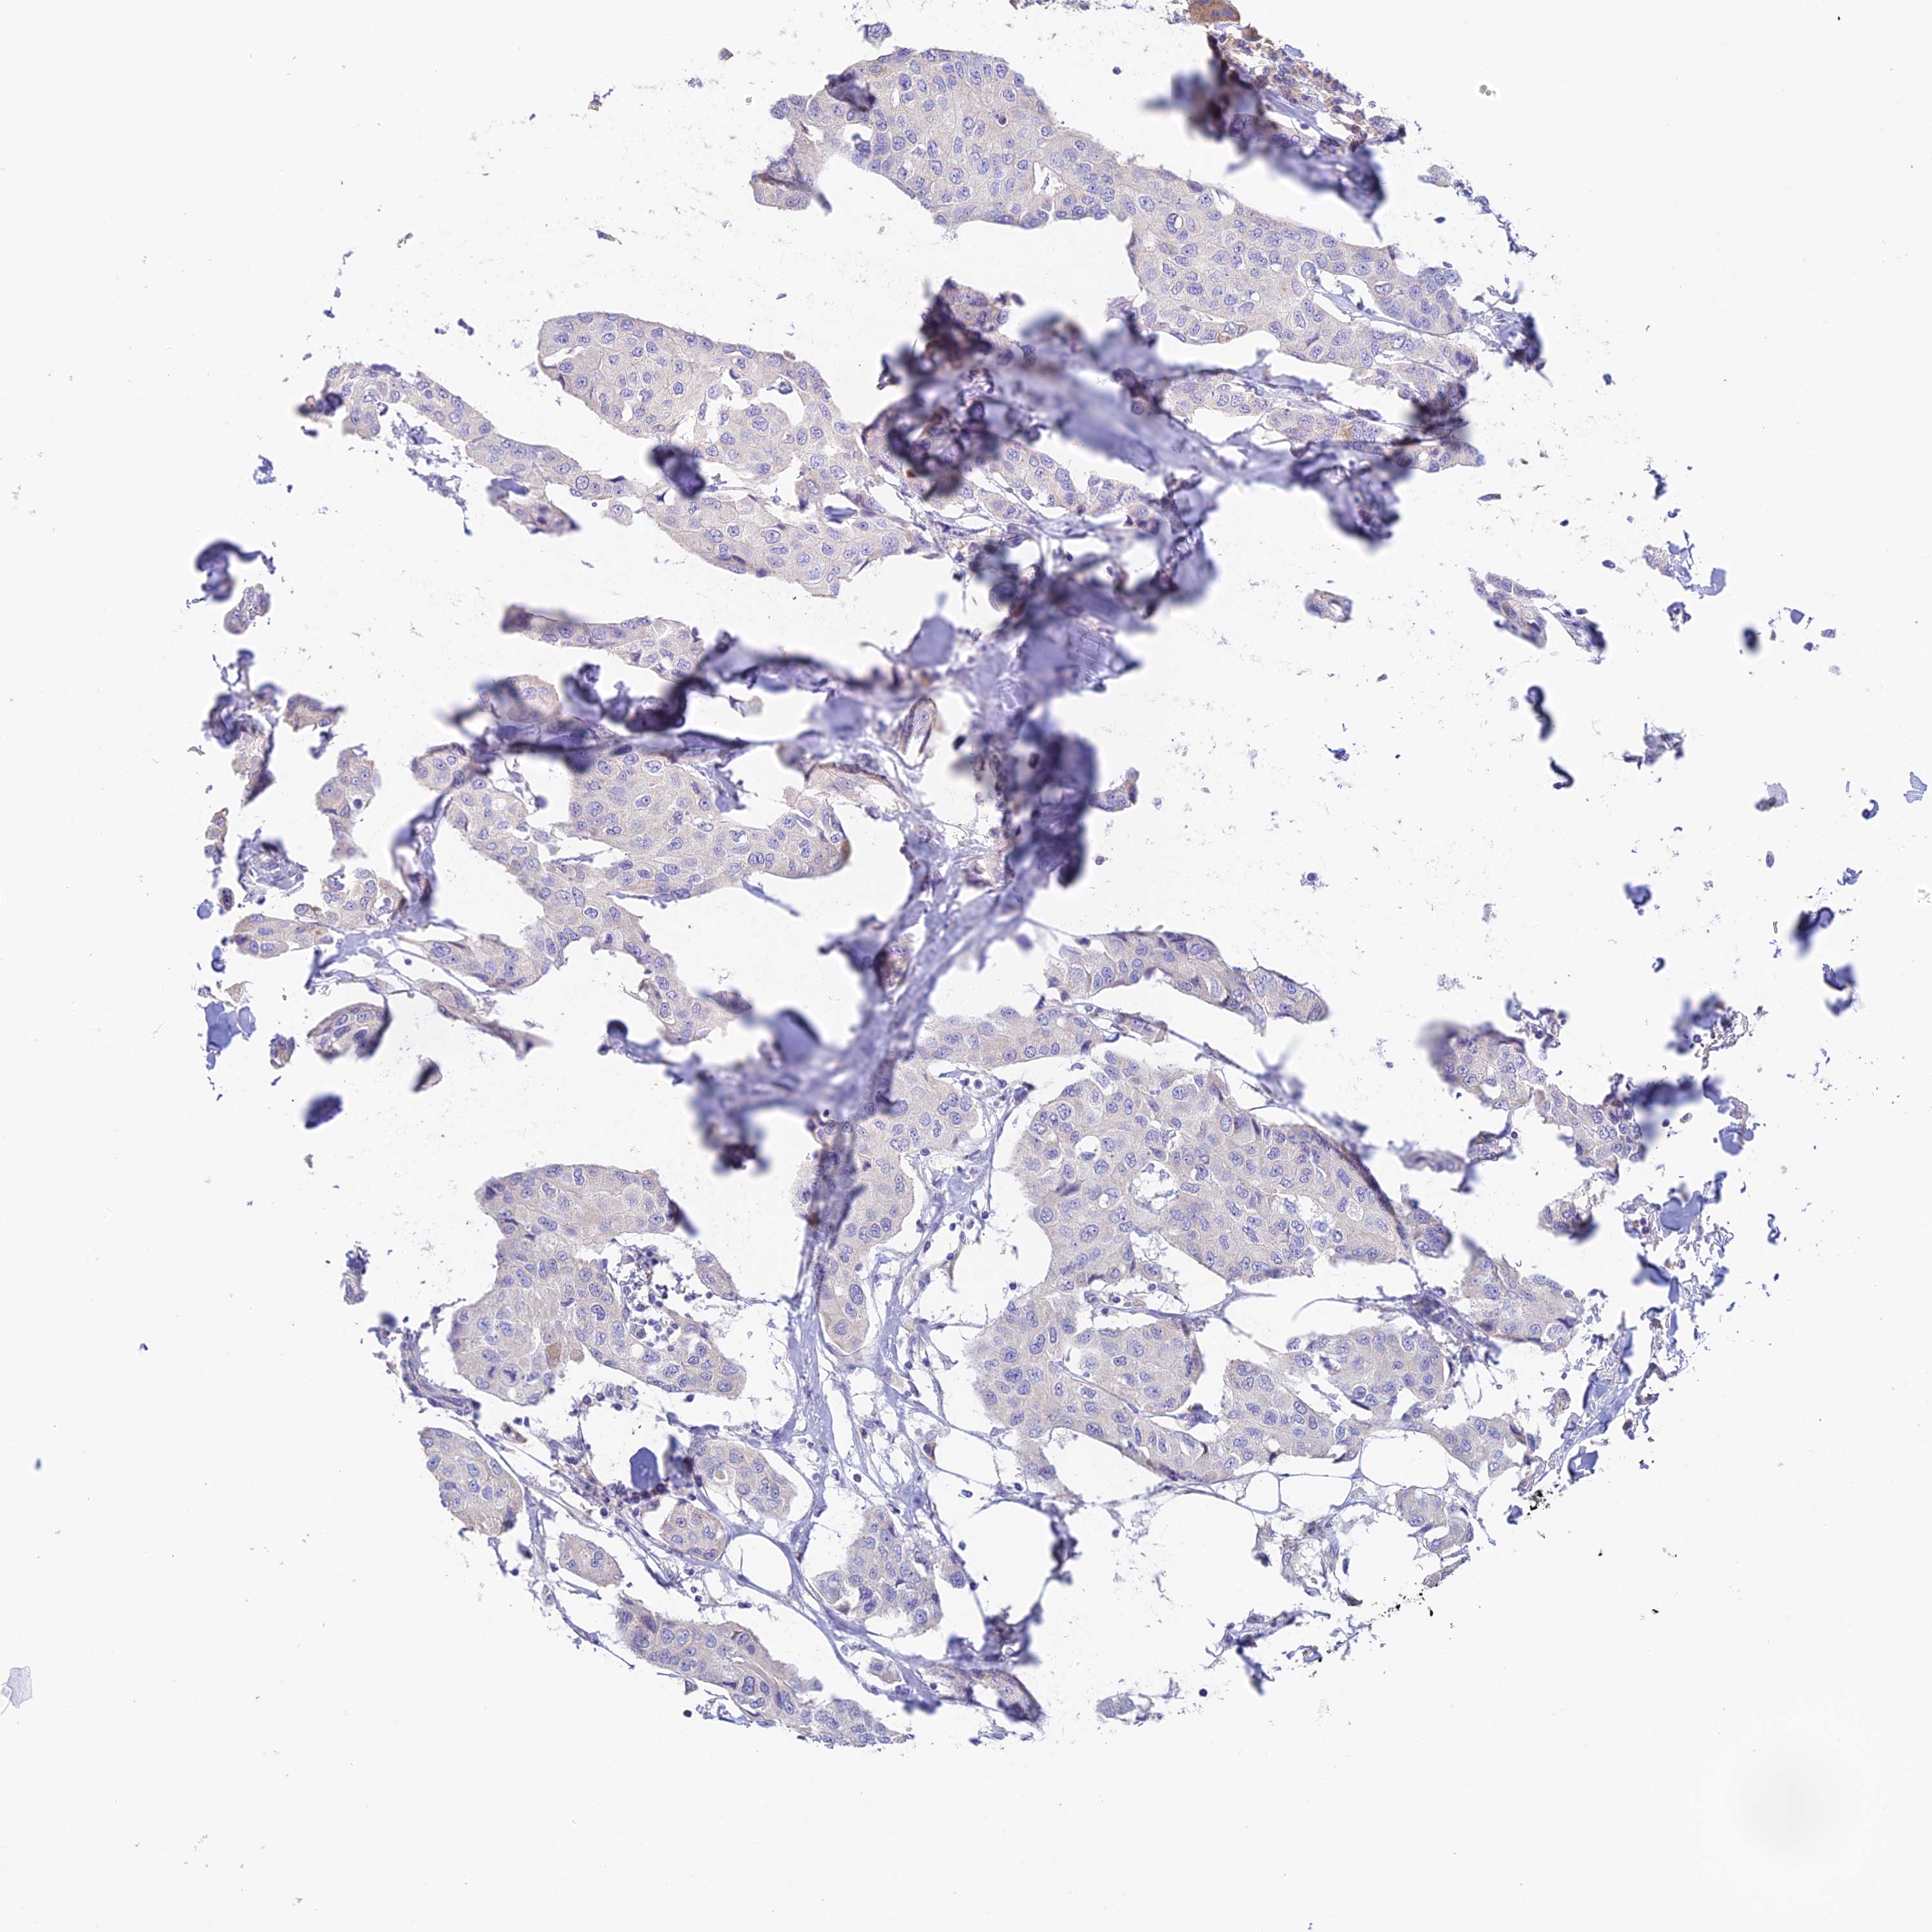

CANCER BREAST CANCER Show tissue menu

BRCA TCGA BRCA VALIDATION PROTEIN EXPRESSION